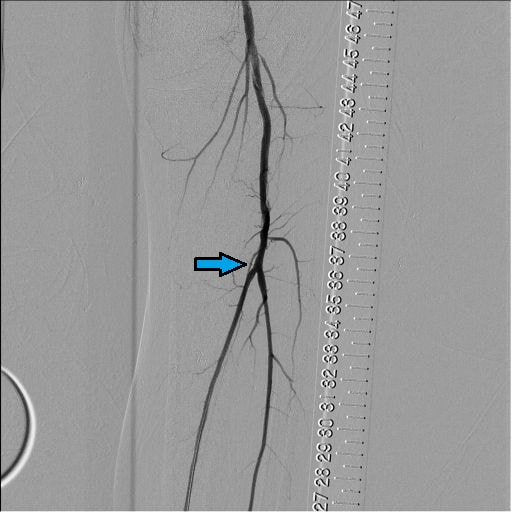

図8.BK Pre画像

Pop以遠の造影。Popに狭窄、trunk(矢印部)とATAの閉塞が認められる。